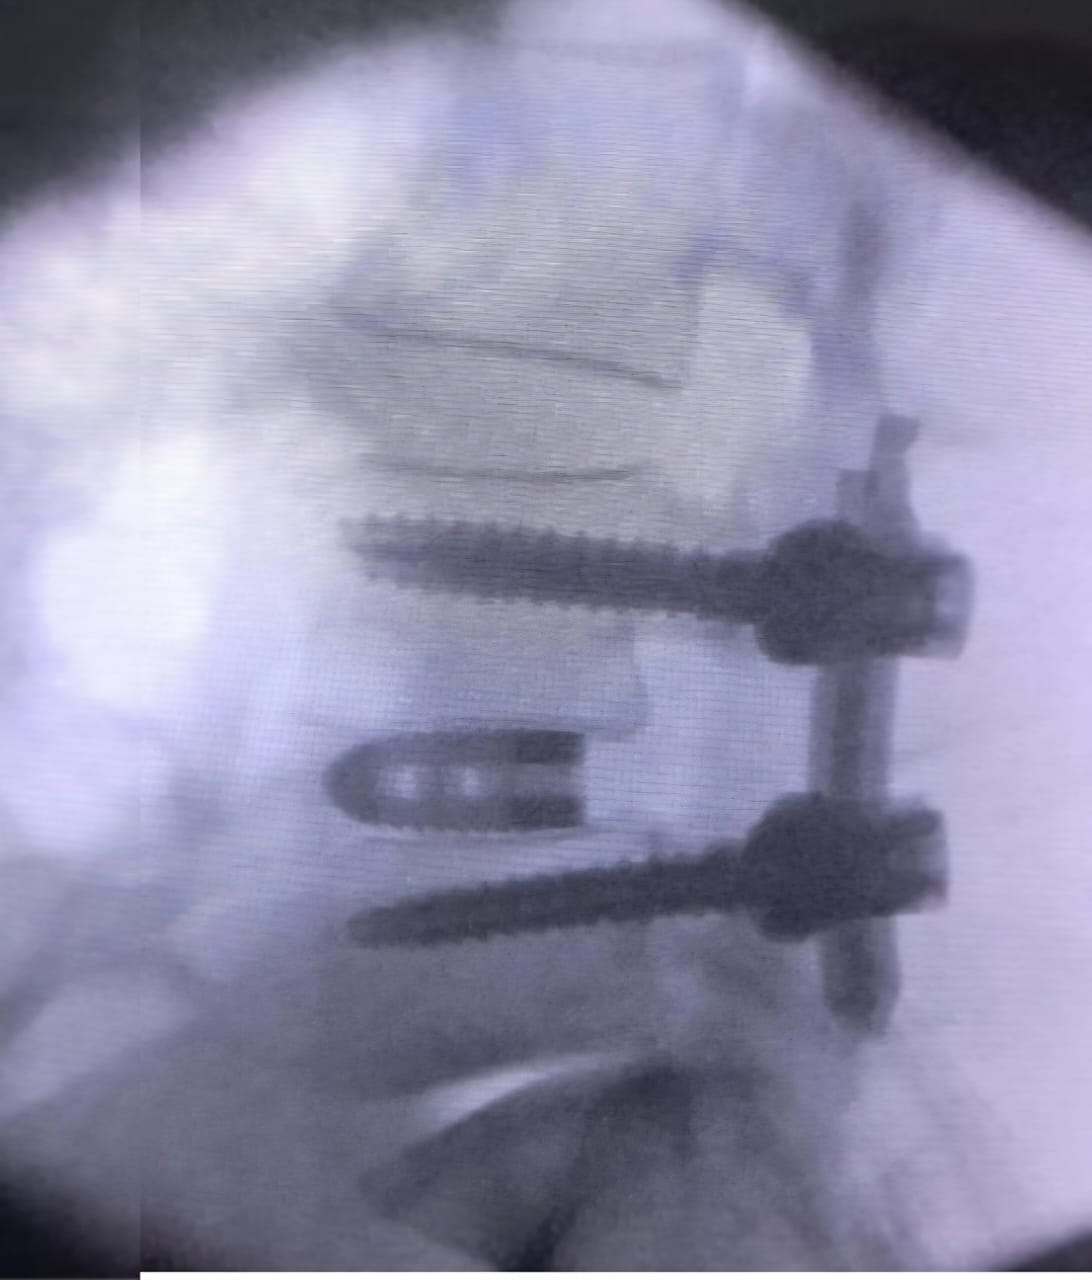

The Treatment

After thorough evaluation, our team opted for a Robotic Endoscopic Transforaminal Lumbar Interbody Fusion (TLIF)*—a next-generation fusion technique that combines:

- Robotic navigation for millimetre-level precision

- Endoscopic visualization for minimal muscle disruption

- Accurate placement of screws and cage for long-term stabili

The surgery was a success, delivering:

- Stable fusion at L4–L5